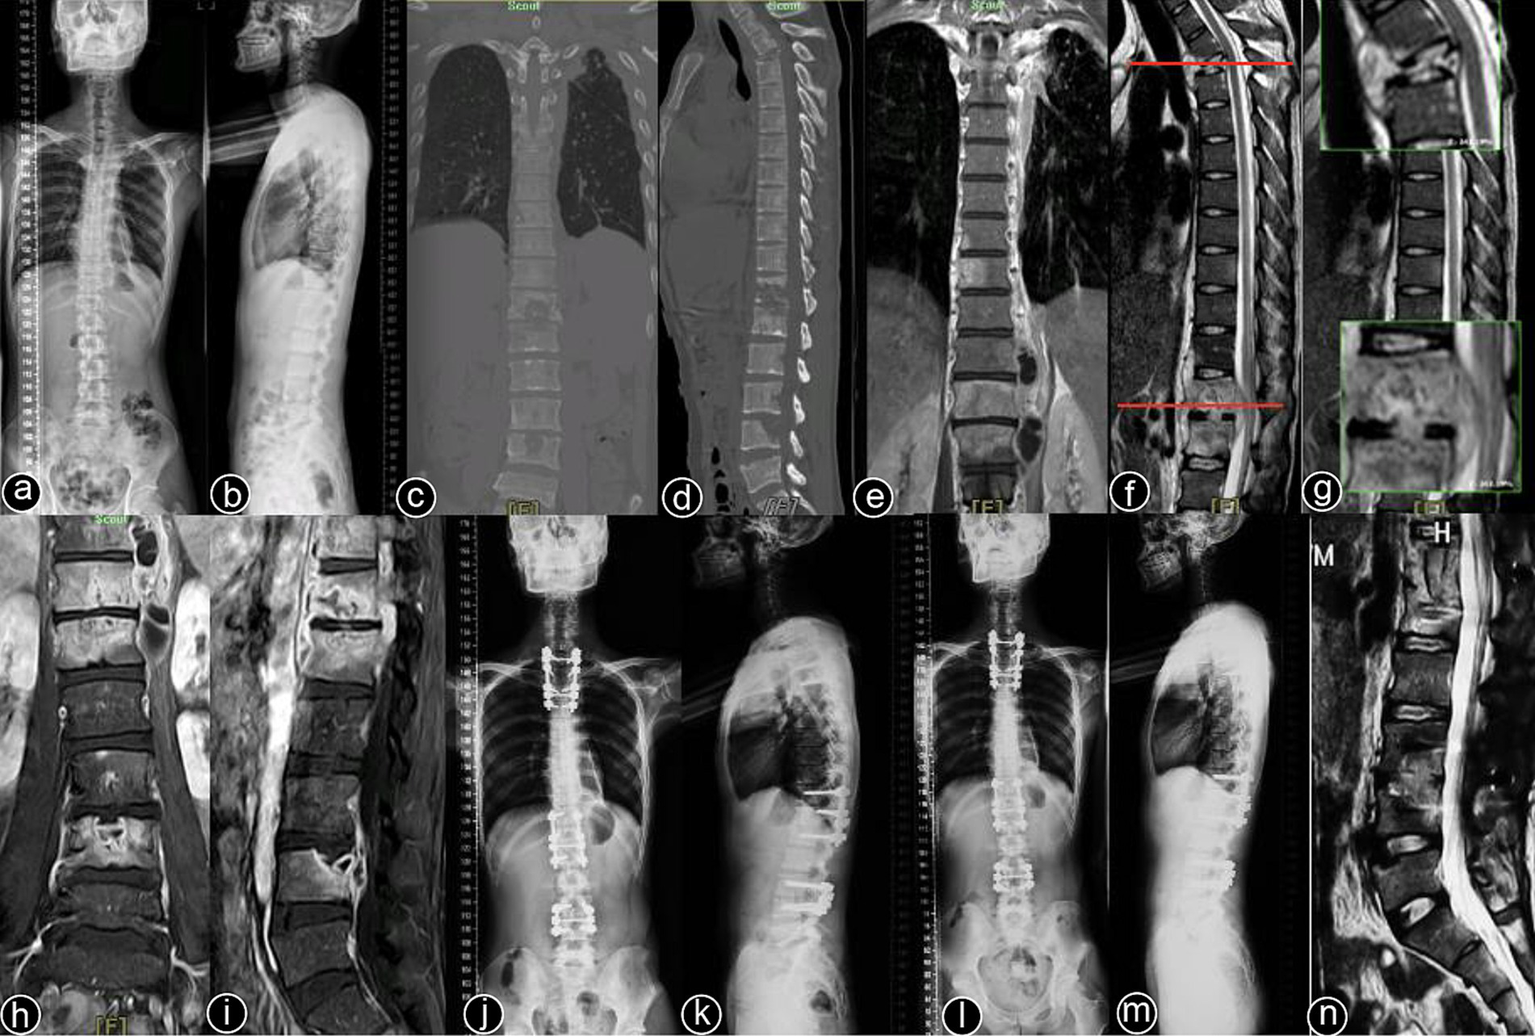

Typical cases are shown in Figures 26, with Figures 24 illustrating intervertebral fixation of the affected vertebrae in three patients from Group A, and Figures 5, 6 demonstrating non-intervertebral fixation in two patients from Group B.

Figure 4

www.frontiersin.org

Figure 4. Patient, male, 45 years old. Diagnosis: spinal tuberculosis (T11–L2). Surgical approach: intervertebral surgery. (A,B) Preoperative anteroposterior and lateral X-rays of the thoracic spine show narrowing of the T11–L2 intervertebral space, significant vertebral destruction, and kyphotic deformity. (C–E) Preoperative thoracolumbar MRI reveals multiple vertebral and accessory signal changes, narrowing of the intervertebral spaces, and a large paravertebral abscess. (F–I) One-month postoperative anteroposterior and lateral X-rays, CT, and MRI of the thoracolumbar spine show short-screw fixation at T11–L2, with proper rib graft placement at the defected segments and a clear spinal canal. (J–L) One-year postoperative anteroposterior and lateral X-rays and CT scans show good fixation with solid bone graft fusion. (M,N) Two-year postoperative lateral X-rays and CT scans. (O–Q) Five-year postoperative lateral X-rays, CT, and MRI of the thoracolumbar spine. (R–U) Ten-year postoperative lateral X-rays and CT scans show stable internal fixation without loosening or breakage, solid bone graft fusion, and no recurrence of the local lesion.

Figure 5

Figure 5. Patient, male, 48 years old. Diagnosis: spinal tuberculosis (T3, T12–L1, L3–L4). Surgical approach: non-intervertebral surgery at T1–T4 and T11–L1; intervertebral surgery at L3–L4. (A,B) Preoperative full-spine anteroposterior and lateral X-rays show unclear visualization of the T3 vertebral body, with roughened anterior margins and narrowed intervertebral spaces at T12–L1 and L3–L4. (C,D) Preoperative full-spine CT reveals multiple non-contiguous vertebral body destructions with paravertebral soft tissue swelling. (E–I) Preoperative thoracic and lumbar MRI show abnormal signal intensities in multiple thoracic and lumbar vertebrae, with narrowed intervertebral spaces and extensive paravertebral abscess formation. (J,K) Immediate postoperative full-spine anteroposterior and lateral X-rays show stable internal fixation at T1–T4, T12–L1, and L3–4. (L–N) One-year postoperative full-spine anteroposterior and lateral X-rays, and lumbar MRI show no loosening or breakage of the internal fixation, a clear spinal canal, and no recurrence of the local lesion.